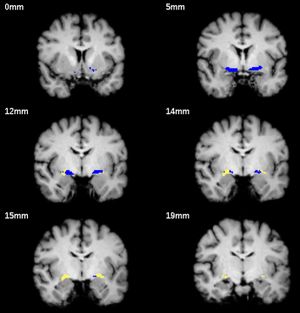

Segmentation example for one brain. The blue ROI refers to CH4, CH4p is shown in yellow. Slices were chosen with the intention to show that CH4p covers a cell cluster often referred to as the Nucleus subputaminalis of Ayala which is rostrolateral extension of the NBM (at 12, 14 and 15 mm). Slice positions are indicated with reference to the most anterior slice on the top left. 3D Slicer 4.3.0 was used to calculate the volume of each labelled region in the map. |